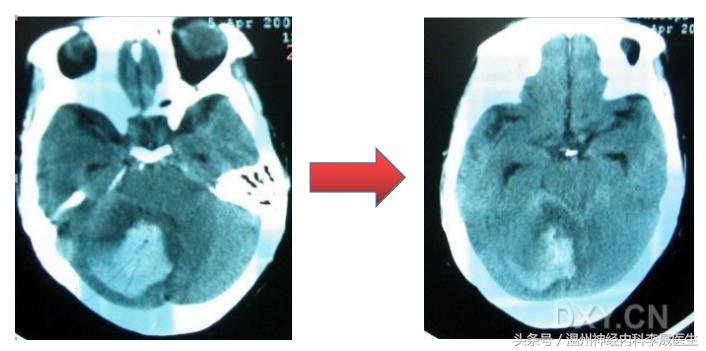

(三)手术指征

1、基底节出血

中等量出血(壳核出血≥30ml,丘脑出血≥15ml)可在合适时机选择微创穿刺血肿清除术或小骨窗血肿清除术,及时清除血种。

大量出血或脑疝形成者,多需外科行去骨瓣减压血肿清除术,以挽救生命。

2、小脑出血,易形成脑疝

出血量≥10ml,或直径≥3cm,或合并脑积水,应尽快手术治疗。

4、脑室出血

轻型的部分脑室出血可行内科保守治疗;

重症全脑室出血(脑室铸形),需脑室穿刺引流加腰穿放液治疗。